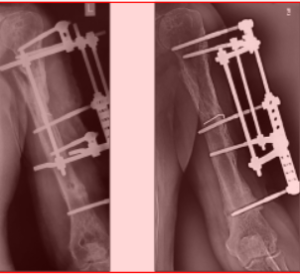

Клинический пример. БольномуЗ., 16лет, с диагнозом: закрытый диафизарный перелом костей правого предплечья со смещением фрагментов, - выполнена операция - остеосинтез АВФ стержневого типа (рис. 1,2).

После обработки операционного поля введены консольные стержневые фиксаторы путем ручного вкручивания в метафизарные и диафизарные отделы костей предплечья. Стержни закреплены с помощью кронштейнов во внешних опорах (рис. 3 - 7).

Аппараты демонтированы через 3,5 месяца. Ось предплечья правильная. Движения в локтевом и лучезапястном суставах в полном объеме (рис. 8).